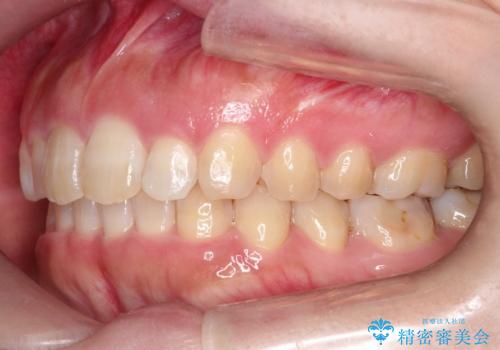

初診時の歯並びの状態としては、上の前歯が下に対して前に飛び出た上顎前突という状態で、前歯は大きく前に飛び出した状態により患者様も口の閉じづらさを感じているとのことでした。また上顎に軽度の叢生(ガタガタ)がありました。

抜歯は行わず上顎の奥のスペースを利用して歯をスライドする方法の他に歯列弓の拡大やディスキング(歯と歯の間の隙間を作る処置)を行い叢生を改善しました。

見た目、嚙み合わせ及び、治療期間や施術内容に大変ご満足いただきました。